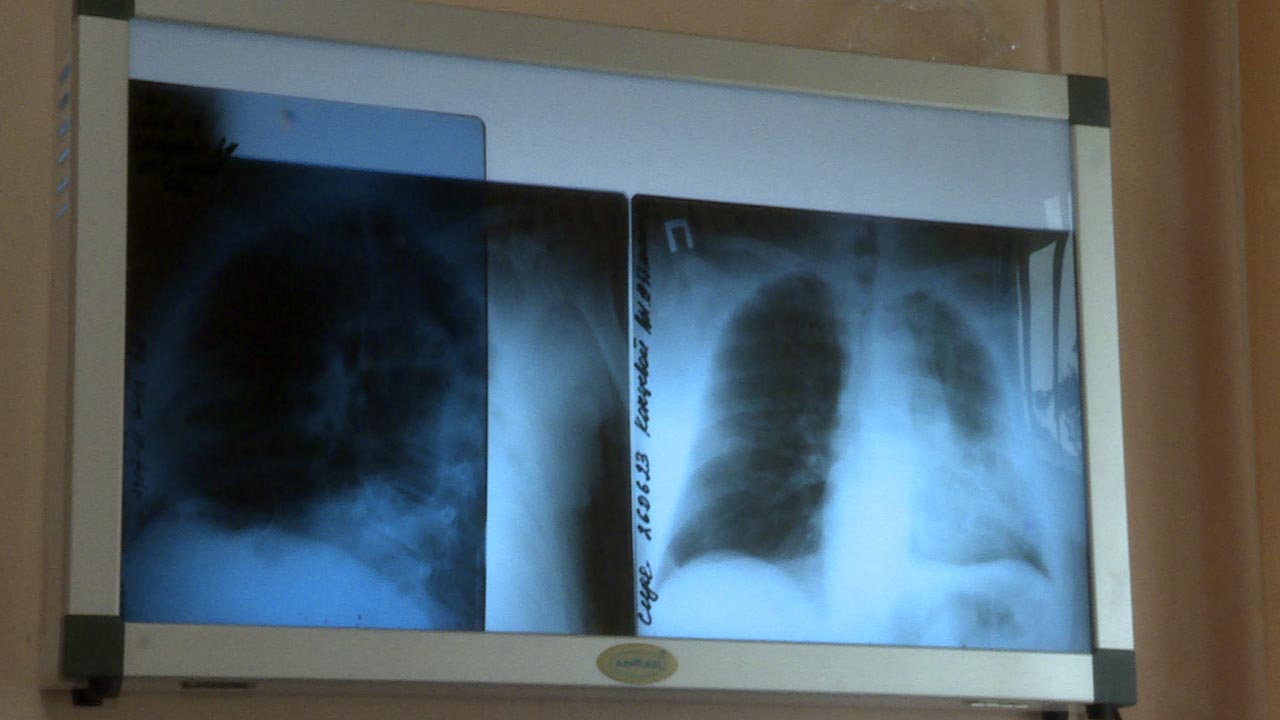

"Вторичная профилактика всех онкологических заболеваний включает в себя ежегодные профилактические осмотры, то есть раннее выявление злокачественных новообразований. Для рака легкого, методом раннего выявления опухоли, является рентген-диагностика, а в идеале это низкодозная компьютерная томография", - объяснил  онколог  Калужского онкодиспансера  Вячеслав Черноусов.

Благодаря опытным специалистам основной процент заболевших выявляется именно при вторичной профилактике, поясняет Вячеслав Черноусов.  А также при рентгенографии, назначающейся перед  плановыми операциями. По статистике это около 25-100 процентов заболевших. И это один из лучших показателей по стране. Еще несколько лет назад показатель в регионе был ниже. Например, из 330 пациентов взятых на учет, при осмотре выявляли  50. Это не всегда пациенты с первой стадией заболевания, но они чаще всего попадают под радикальное лечение и имеют большой шанс на выздоровление.